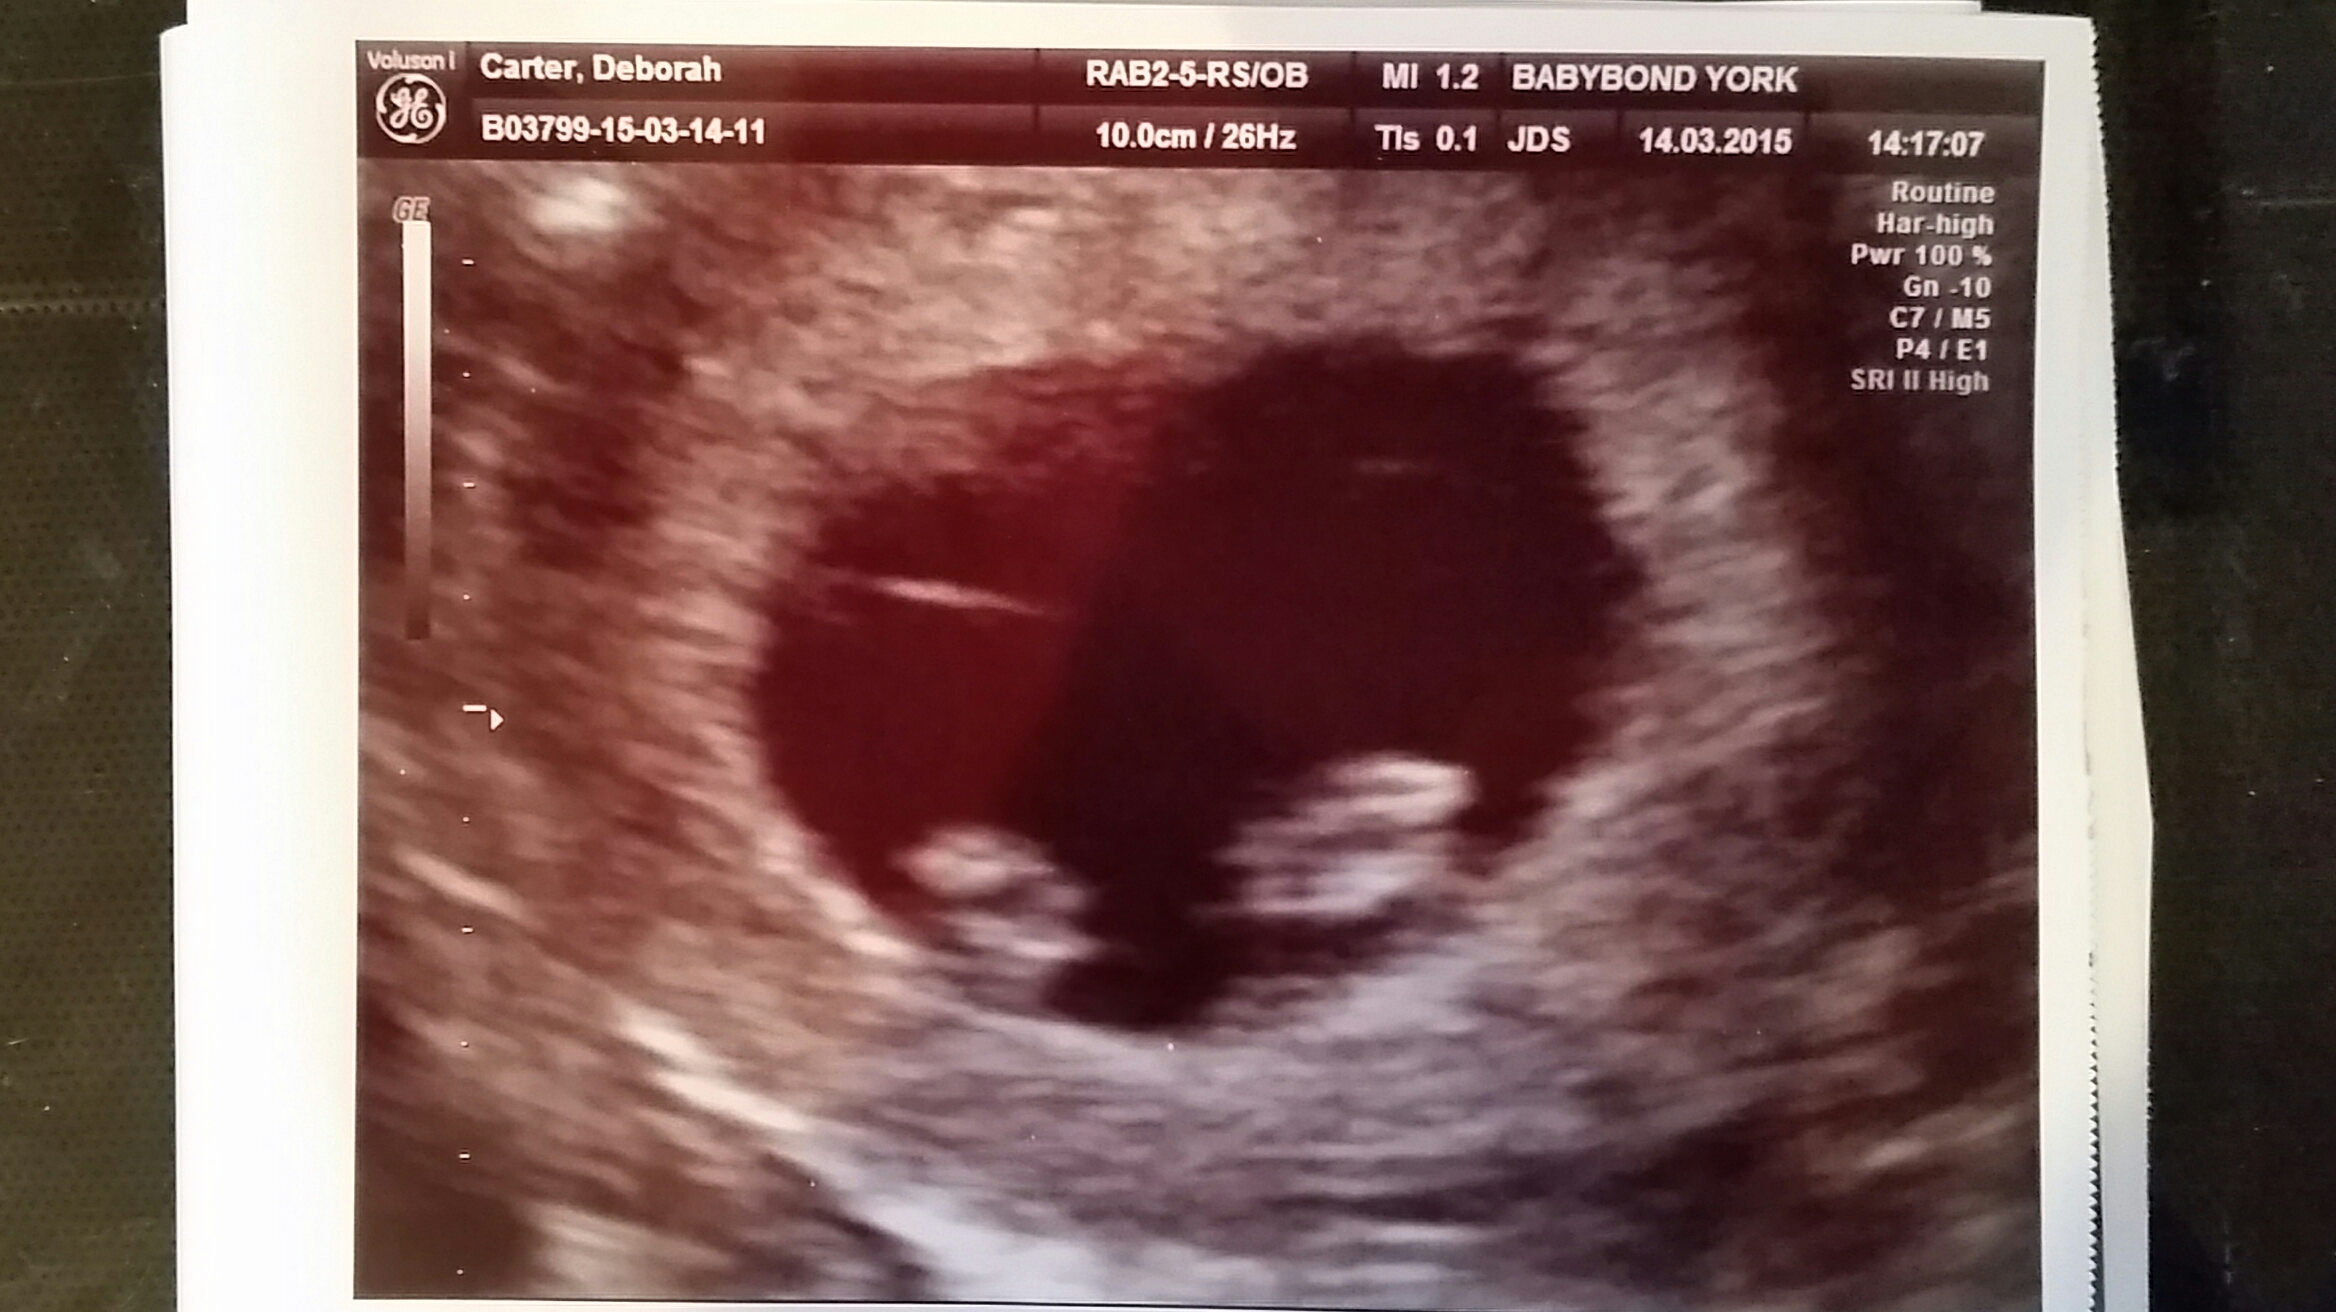

Just had our dating scan today! 8 weeks exactly! Here is cub's head & little arm/leg stumps! I have a cyst in an ovary but was told that should go away. This is our first!